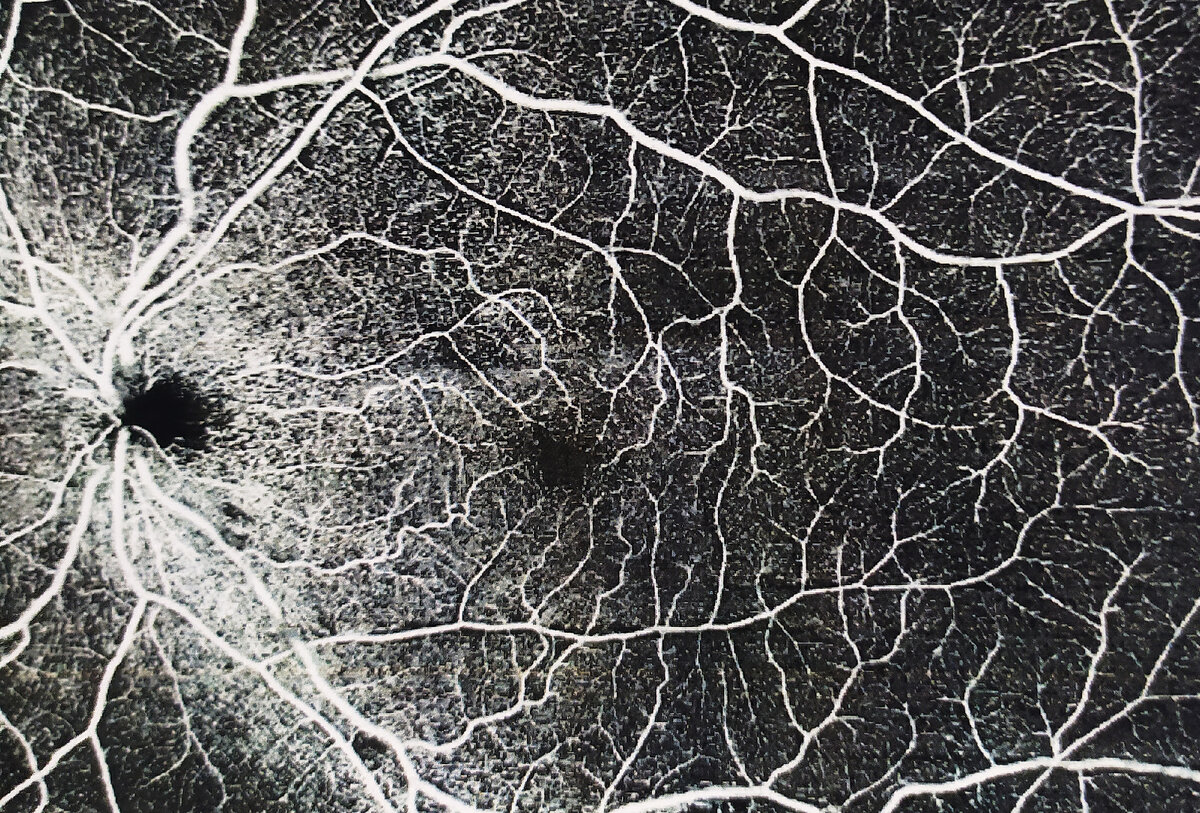

Что же он ищет на этом самом дне? Среди всего многообразия открывающейся перед врачом информации при осмотре беременных его интересуют 2 зоны: первая это центр сетчатки – здесь оценивается зрительный нерв, сосуды, область макулы (макула – это зона сетчатки с наибольшей остротой зрения) и вторая зона - крайняя периферия. Патология центральной сетчатки у беременных на приеме встречается, к счастью, крайне редко – обычно выявляется в стационаре при тяжелых гестозах и другой сопутствующей патологии. Гораздо чаще встречаются «проблемы» на периферии сетчатки, которые при грамотном подходе проблемой вовсе не являются. Скорее всего Вас отпустят «в естественные роды» без каких либо оговорок, ну, в ряде случаев, предложат процедуру лазерного укрепления проблемных зон.

Белые точки (лазерные ожоги) вокруг опасных зон на сетчатке (вид сразу после лазерной коагуляции)

Это лазерное вмешательство не несет особого дискомфорта, субъективно немногим отличается от осмотра, является надежным, безболезненным и безопасным методом. Такое лечение предлагают при выявлении дистрофий и разрывов сетчатки, которые в будущем (и вовсе не обязательно при родах) могут привести к её отслойке.